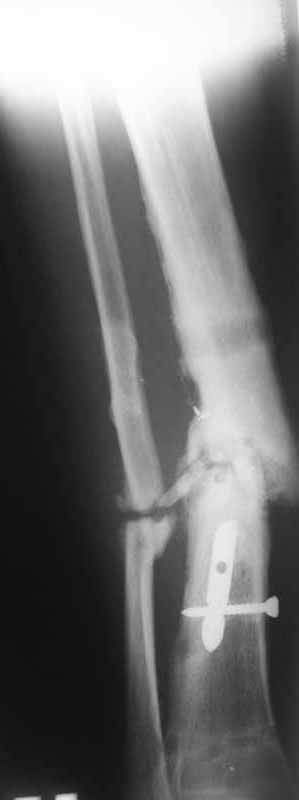

Это гипотрофический ложный сустав. Проблем видится несколько:

1. нарушение трофики в месте перелома.

2. после фиксации в аппарате Илизарова на рентгеногнрамме имеются признаки спицевого остеомиелила. В настоящи момент хотя свищей нет с мая 2011 нет опасно ли фиксировать голень стержнем?

Про восстановление кровообращения. Микрохирургически посадить малоберцовую кость? Есть ли у кого опыт?